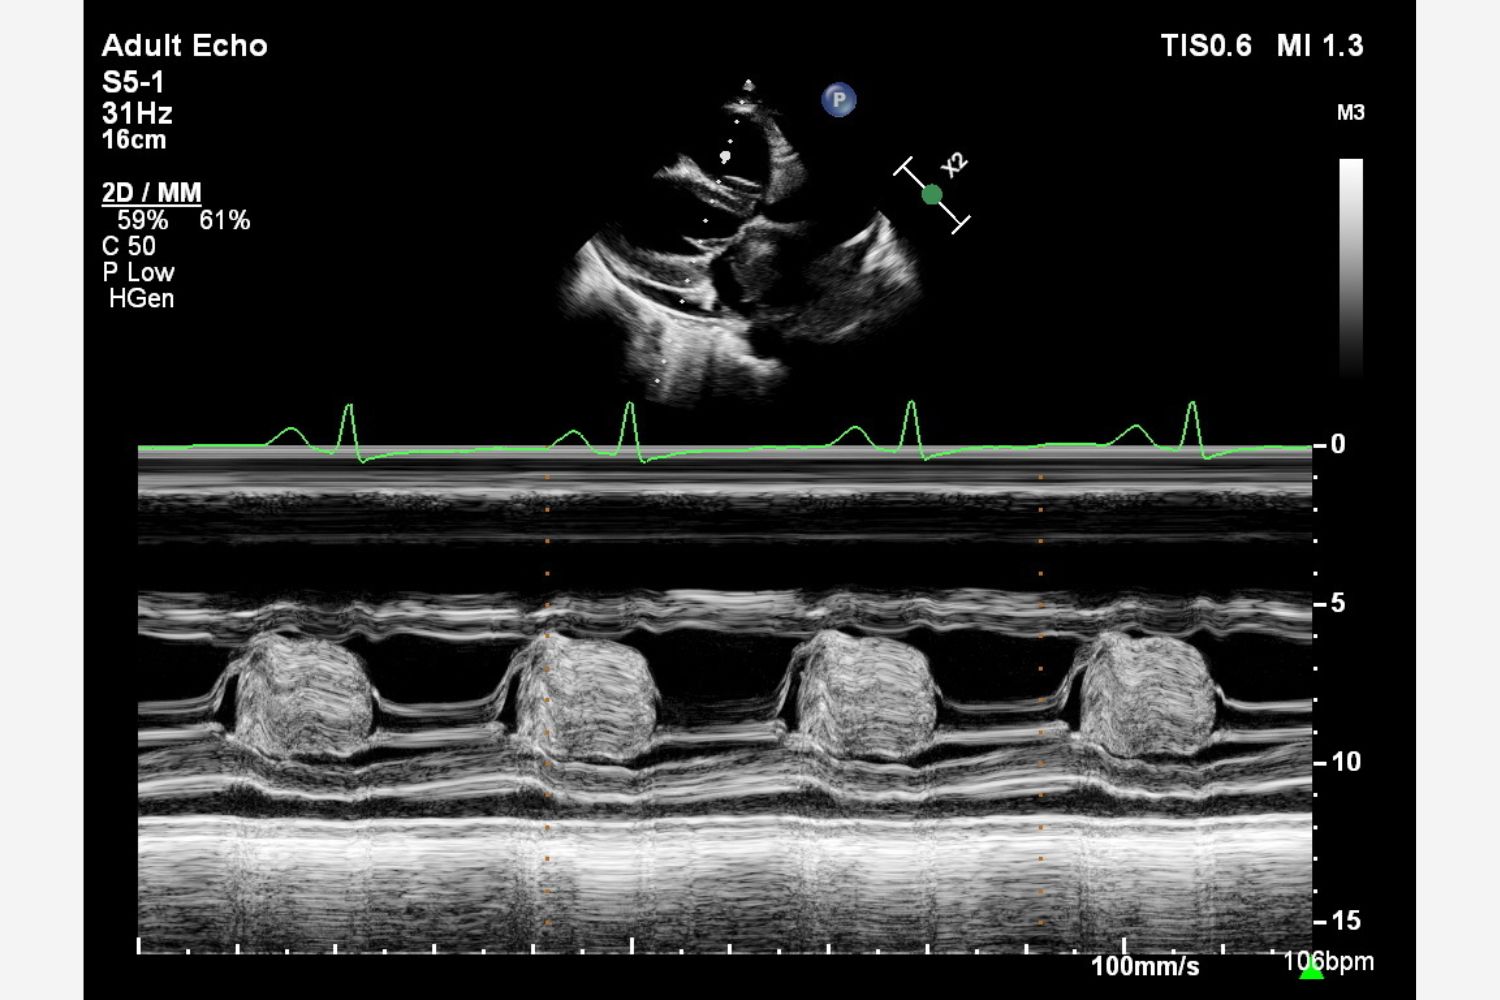

Image of the Week - 12 June 2024

Doctor Wei Fen Tay

Doctor Galal Abushahba